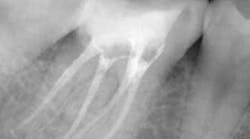

Using either a round or football bur, open the pulp chamber. With an endodontic explorer, locate all the canals in the chamber.

Once the canals are located, I’ll use a 0.10 Sybron TF rotary file to enlarge the coronal third and remove pulp tissue. Now that the canals are visible, widen the coronal portion further using Gates Glidden. Flaring the coronal portion is vital to preventing file fractures and ensures adequate instrumentation and irrigation during the procedure. All of the canals should be easily visible for good access.